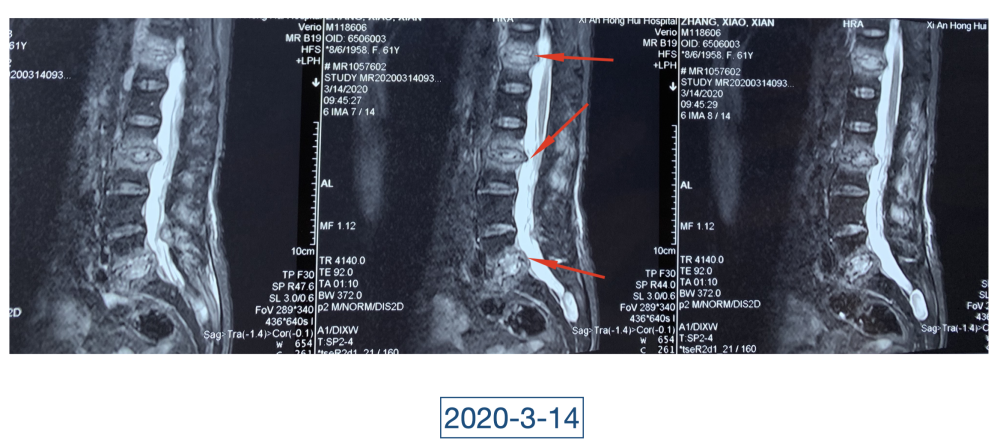

经过科室讨论、会诊,李辉也查阅了很多资料,按照黄大娘的症状,他跟之前的接诊医生一样,觉得应该是骨关节感染。可之前的穿刺、培养各种检查也做过,为什么没有找到致病菌?李辉想,或许是检查中出现了问题,没有查对地方。于是他决定,在B超引导下骨穿刺,通过最新技术精准定位病灶,只有这样也许才能抓到真正的“罪犯”。

在黄大娘入院第四天,李辉将她推入检查室,结果很快出来了,为烟曲霉菌感染。这个结果验证了李辉的想法,也解释了此前抗感染药物为何一直不奏效。“找到元凶就好办了,对症用药就可以。真菌感染本来治疗时间就很长,骨科类感染灶治疗时间更长,用了5个月的时间,终于治好了。”